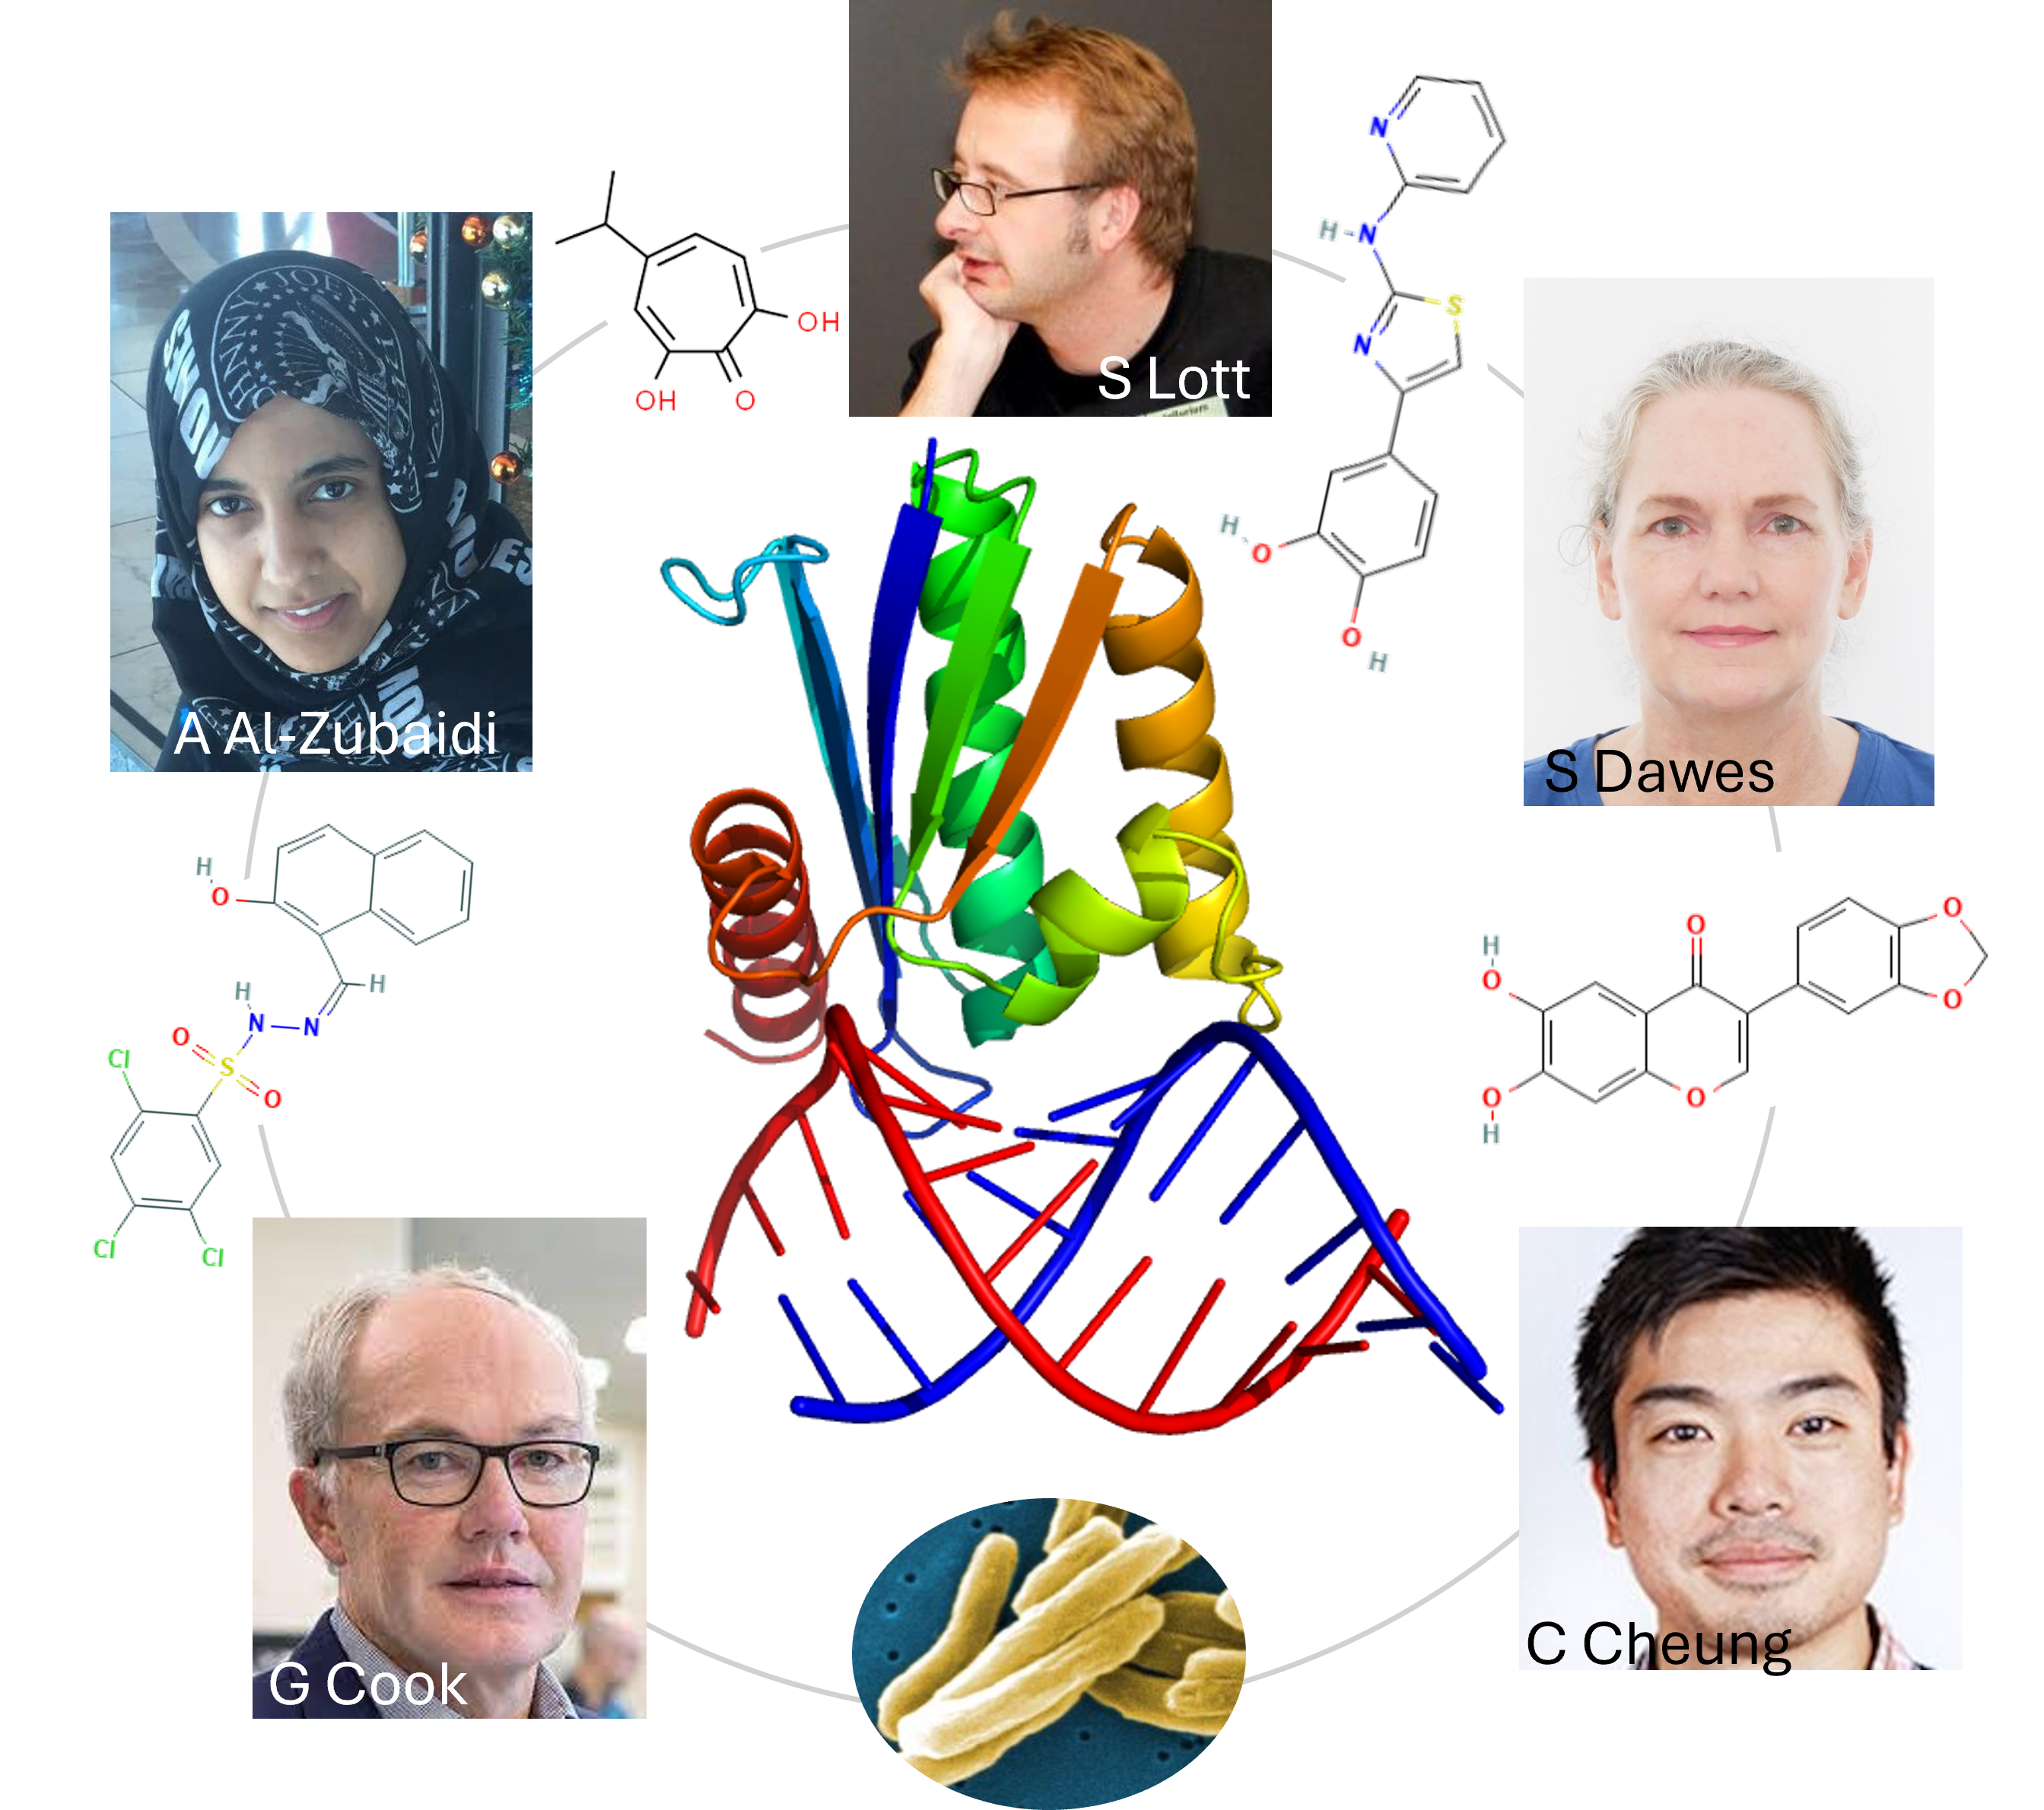

New avenues in fight against drug resistant TB

While rising drug resistance in Mycobacterium tuberculosis is eroding the power of almost all available antibiotics in the fight against this major pathogen, work completed by MWC-

read the full story

Flagship launches careers of young investigators

The MWC Tuberculosis Flagship research programme has proved to be a great springboard for younger investigators to progress their careers.

read the full story

High-impact publications highlight TB research

Researchers in the MWC’s Tuberculosis Flagship Research Programme have had their long hours in the lab recognised through publications in world-leading journals.

read the full story

Early career researchers zoom in on an important drug target

An estimated 1.3 million people die from tuberculosis (TB) each year, and new drugs are desperately needed, especially as resistance to existing drugs increases.

read the full story

Stepping up the fight: The Tuberculosis Flagship (2013)

The Maurice Wilkins Centre is behind the launch of a national research network of ‘serious intellectual muscle’ that aims to speed up action against tuberculosis.

read the full story

New inhibitor for tuberculosis (2011)

A new way to shut down the bacterium responsible for tuberculosis has been devised by researchers in one of the Maurice Wilkins Centre’s longest-standing collaborations.

read the full story

Modern approaches to an ancient disease (2010)

Scientists associated with the Maurice Wilkins Centre have created new drugs for tuberculosis.

read the full story